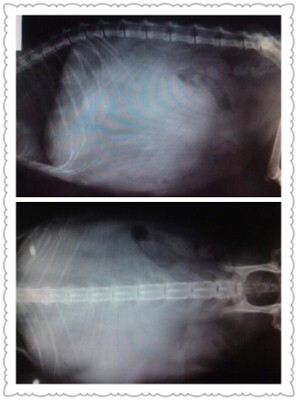

主題: 明道二街 大面積腫瘤 的玳瑁母貓 申請者姓名: 劉雅雲 花色: 申請日期: 2012-08-07 07:47:22 申請者部落格: 申請者臉書網址: 所在縣市/合作醫院: 高雄市/樂生動物醫院 治療費用: 5400元 需求人數: 13人 已結案 (2012-12-08 19:09:43) 報名人員: 楊灰兔(已付款)、POPO(已付款)、Florence(已付款)、陽光小猴寶(已付款)、冥王星獅子(已付款)、Bei Bei Wang(已付款)、Bei Bei Wang(已付款)、珮小君(已付款)、saray、Icelady Yin(已付款)、黃桔子(已付款)、Wendy Jiang(已付款)、saray(已付款)、范立縈(已付款)、 候補人員: Rachel、E、 動物病情說明: 這是誘捕結紮的母貓, 醫生麻醉要做結紮手術, 發現貓咪有很大的腫瘤, 本以為是漲奶, 但因為硬硬的, 醫生告知須要做X光及進一步的檢查. 照了X光後, 確定是腫瘤, 面積很大, 開刀下去發現, 腫瘤已經擴散到了其他器官, 不能切除腫瘤, 不然貓咪可能會沒命. 醫生只好進行縫合, 因為貓咪食慾各方面都算正常, 所以目前找到朋友可以安寧照顧, 希望她剩下不久的日子可以吃的好, 不用在街頭流浪了.

醫療明細如下:

X光 x2 = 800

驗血 1500

氣體麻醉1000

住院 7/4 - 7/11 七天 X 300 = 2100